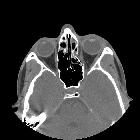

- orbital emphysema: especially when the fracture is into an adjacent paranasal sinus (see: black eyebrow sign)

Inferior blowout fracture

Inferior blowout fractures are the most common. Orbital fat prolapses into the maxillary sinus and may be joined by prolapse of the inferior rectus muscle. In children, the fracture may spring back into place (see trapdoor fracture). Most fractures occur in the floor posterior and medial to the infraorbital groove .

CT

CT is the modality of choice for assessment of the facial skeleton. A full assessment does not require the administration of contrast. Ideally, the acquisition should be performed using the thinnest detector settings, enabling thin-slice reconstructions along three orthogonal planes with a bone algorithm. Additional soft tissue algorithm reconstructions using larger slice thickness and 3D volumetric reconstruction are useful for assessing associated soft tissue injury and gauging facial asymmetry, respectively.

In addition to evaluating the location and extent of fracture(s), other features requiring assessment and reported include:

- prolapse of orbital fat